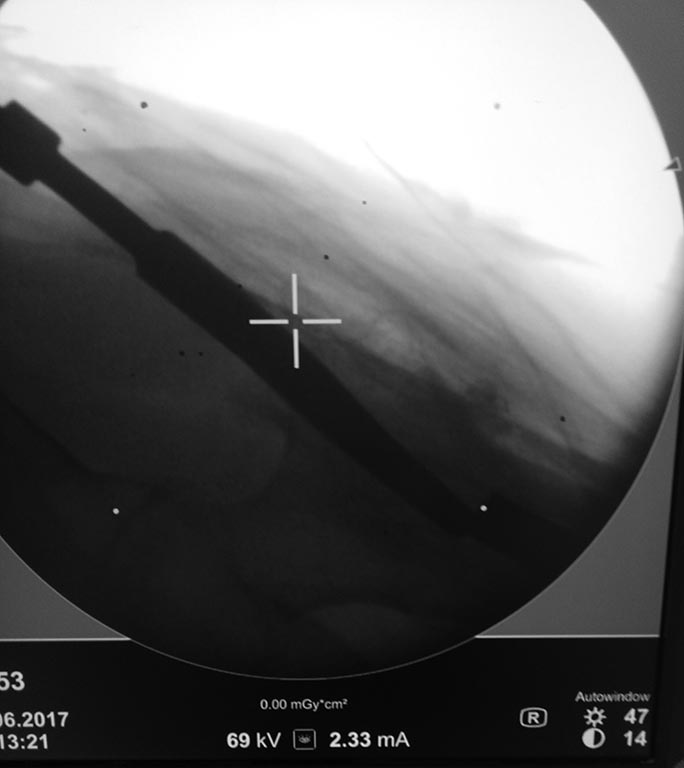

Доброе утро коллеги!фикшен с бедра удалили, сидел очень плотно.

На ортопедическом столе уложили, ногу согнули, как на ретроградное бедро, артротомия, релиз 4-главой, увеличили обьем движений. Далее попытка выбить плечевым, голенным штифтом не сильно имела успех. Стоял на своем. Проксимально по направителю рассверлили канал развертками 11,12. В итоге взяли 11 фемор санатметал, несколько ударов, и он вылетел из бедра!